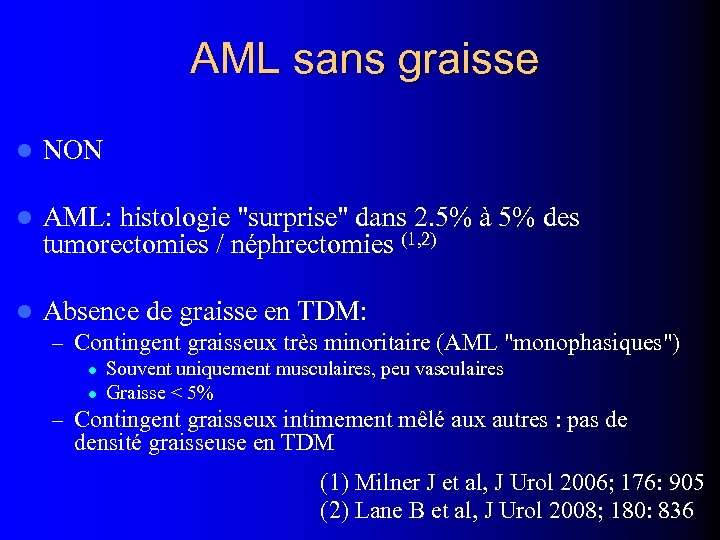

AML sans graisse l NON l AML: histologie "surprise" dans 2. 5% à 5% des tumorectomies / néphrectomies (1, 2) l Absence de graisse en TDM: – Contingent graisseux très minoritaire (AML "monophasiques") l l Souvent uniquement musculaires, peu vasculaires Graisse < 5% – Contingent graisseux intimement mêlé aux autres : pas de densité graisseuse en TDM (1) Milner J et al, J Urol 2006; 176: 905 (2) Lane B et al, J Urol 2008; 180: 836

AML sans graisse l NON l AML: histologie "surprise" dans 2. 5% à 5% des tumorectomies / néphrectomies (1, 2) l Absence de graisse en TDM: – Contingent graisseux très minoritaire (AML "monophasiques") l l Souvent uniquement musculaires, peu vasculaires Graisse < 5% – Contingent graisseux intimement mêlé aux autres : pas de densité graisseuse en TDM (1) Milner J et al, J Urol 2006; 176: 905 (2) Lane B et al, J Urol 2008; 180: 836